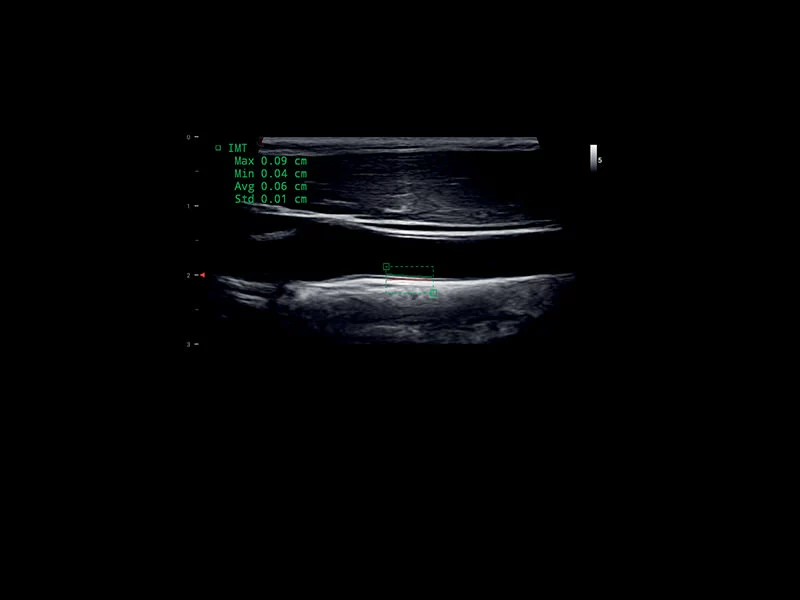

MyLab™9 Platform - QIMT Intima-media thickness quantification based on radio frequencies in real-time studies

MyLab™9 Platform - QIMT Intima-media thickness quantification based on radio frequencies in real-time studies